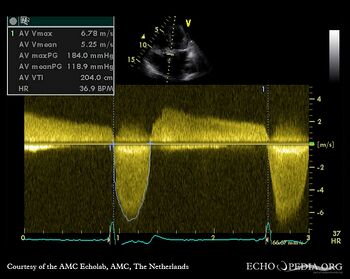

| A5CH: severe aortic valve stenosis

Continuous-wave Doppler signal of severe aortic valve stenosis, peak gradient 184 mmHg